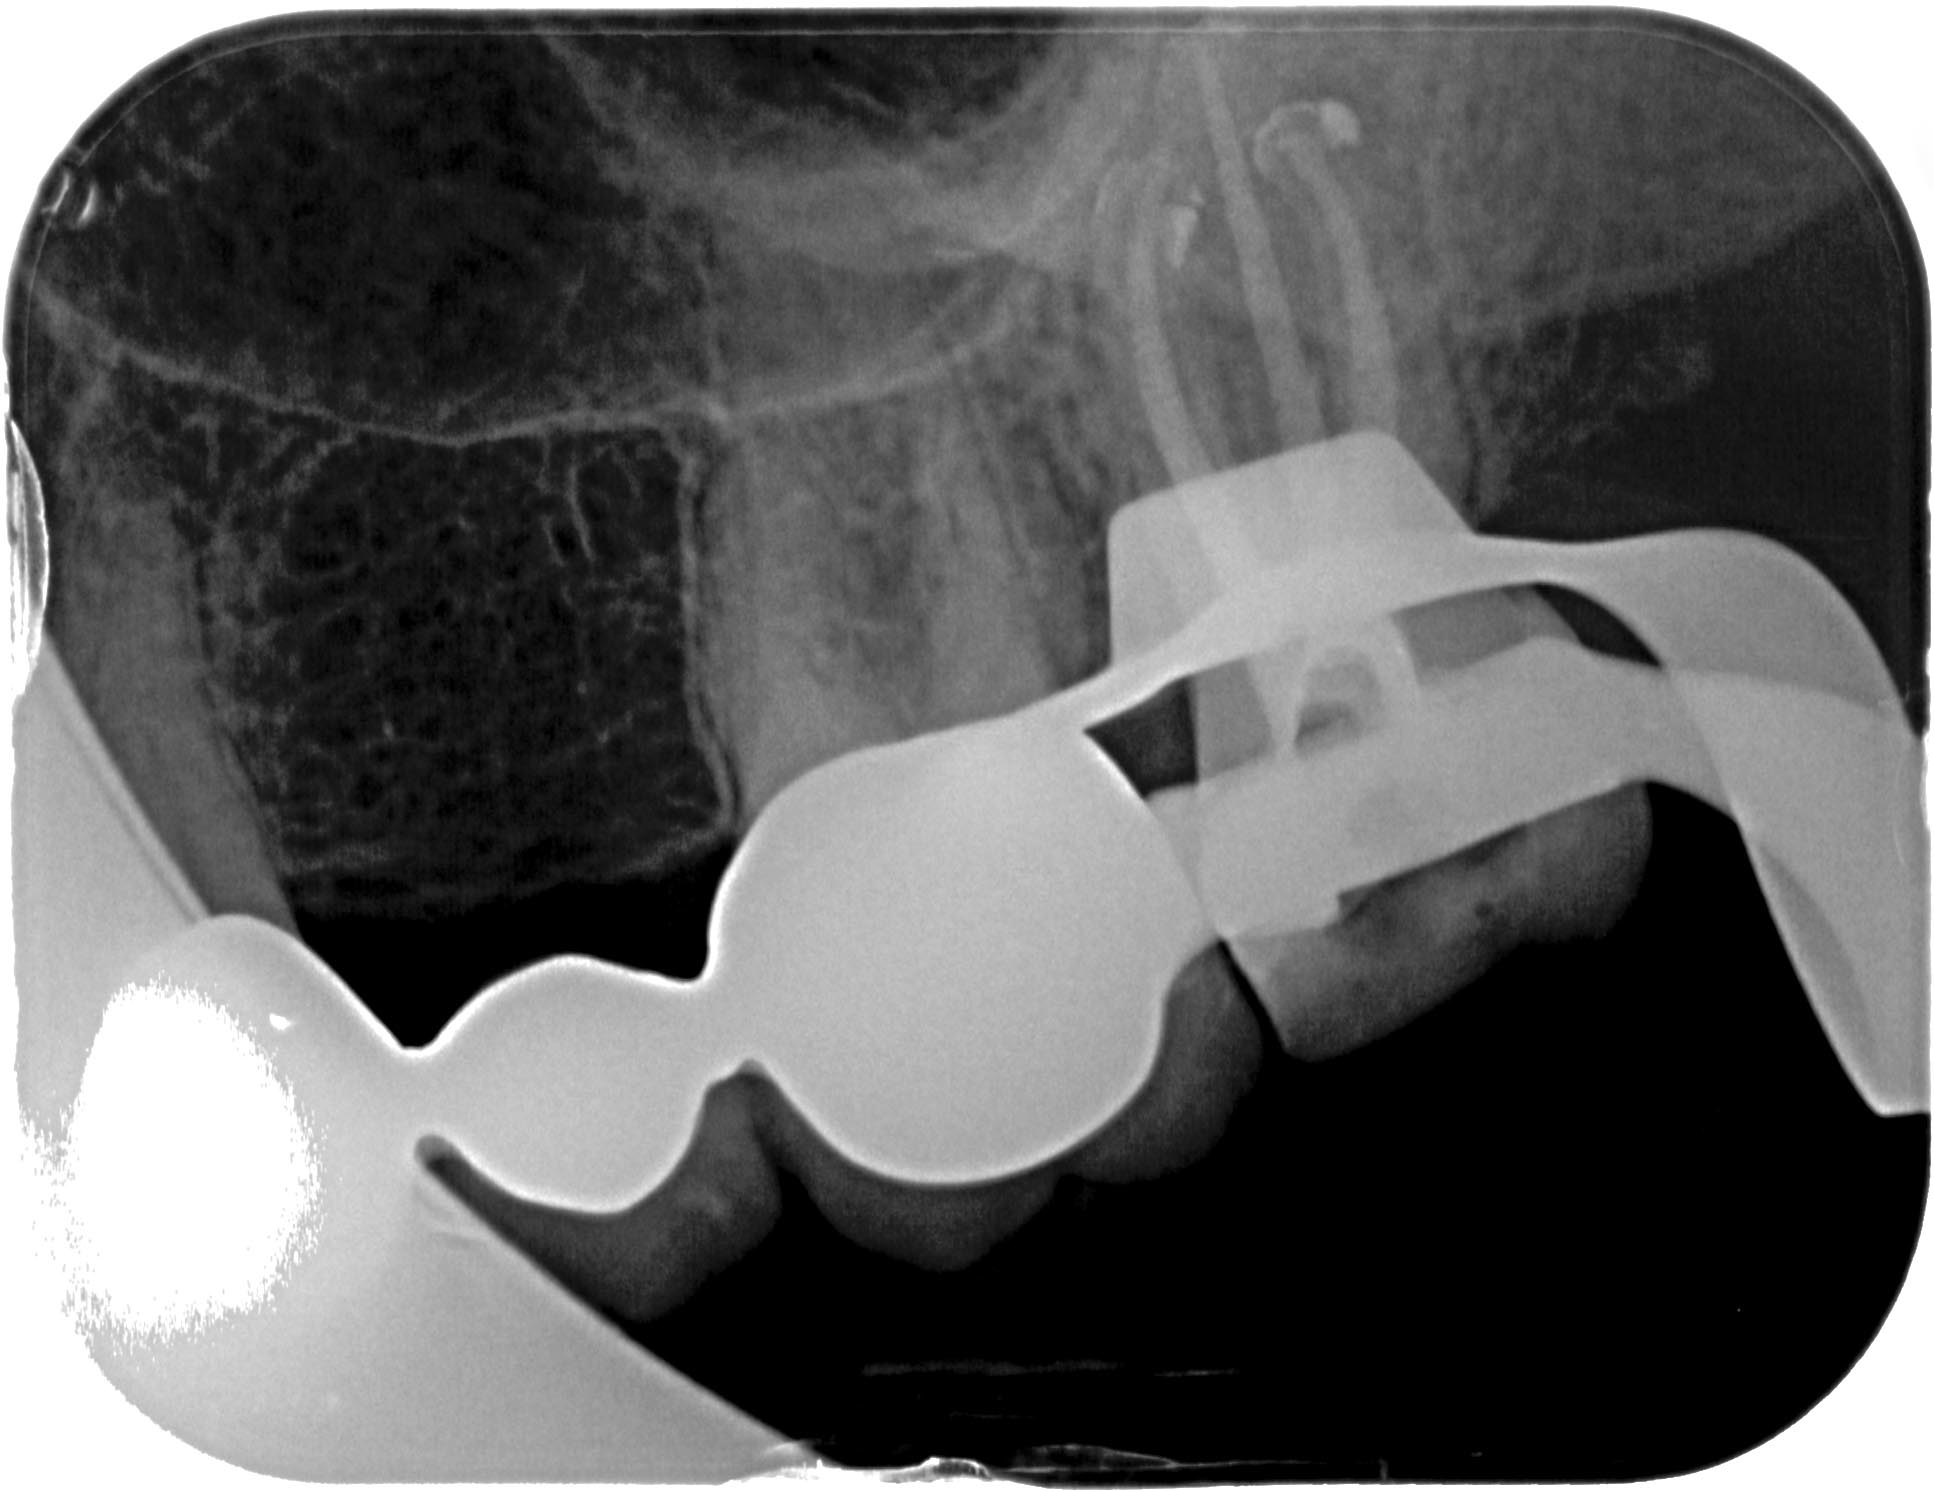

SE_27-2 Veröffentlicht 4. Mai 2014 am 1934 × 1492 in Massive apikale Aufhellung an Zahn 27 im Recall WF- Kontrolle exzentrisch